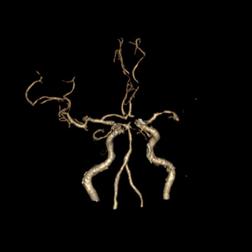

十七、基底动脉延长扩张合并开窗畸形

病例31:基底动脉延长扩张合并基底动脉起始段开窗畸形

病例32:基底动脉扩张延长合并基底动脉近段开窗畸形

病例33:左侧大脑前动脉A1段开窗畸形合并基底动脉延长扩张